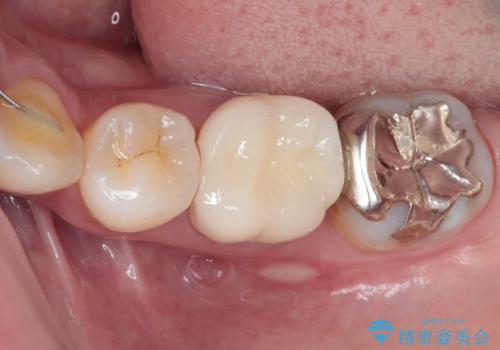

最新の症例

Latest cases